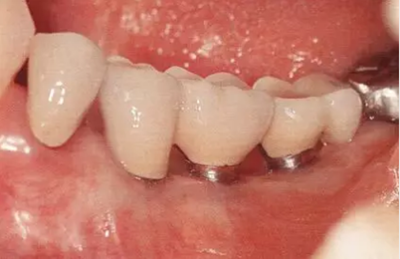

▲圖7-1,2

圖7-1 Type2-Class2的病例,頰側牙槽嵴基本沒有角化齦,需要增大角化齦的寬度。

圖7-2 第二次種植手術時佩戴愈合基臺后的狀態(tài)。舌側進行APF,頰側進行FGG以獲得角化齦。

圖7-3 第二次手術后3個月的狀態(tài)。頰舌側都有足夠的角化齦。

▲圖7-4

第二次手術后4個月的狀態(tài),口腔前庭較深,舌側角化齦寬度充足。